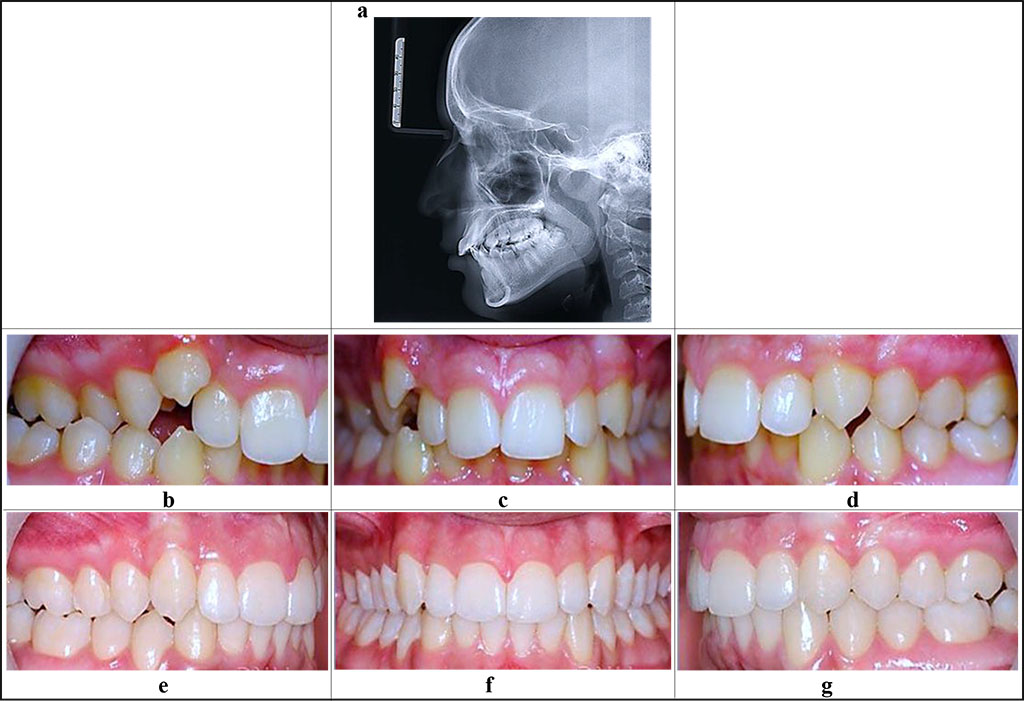

Figure 3 shows the periodontological status and the occlusal relationships in a patient with abnormal dental arch ratios (K07.2; ICD-X), abnormal teeth position (K07.3; ICD-X) associated with UCTD (moderate degree).

Figure 3. Patient E., 16 y.o. Diagnosis: chronic catarrhal gingivitis, moderate severity (K 05.10). Distal occlusion (closure of first molars and canines, Angle’s Class II; 07.20), protrusion of the upper front teeth. Teleroentgenogram, lateral projection (a), periodontological status and occlusive relationships prior to (b-d) and after (е-g) the orthodontic treatment.